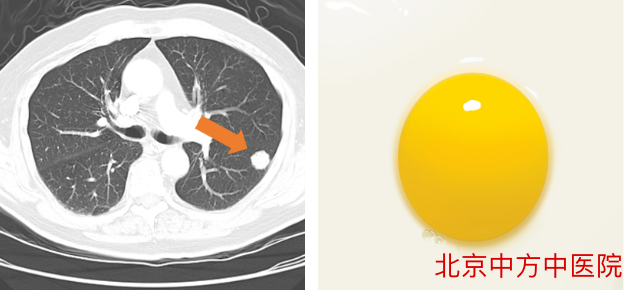

2、实性结节

结节的密度很高,完全不透明了,好比我们的鸡蛋黄一样(如右图)结节内部有填充物,看不到后面的肺纹理。